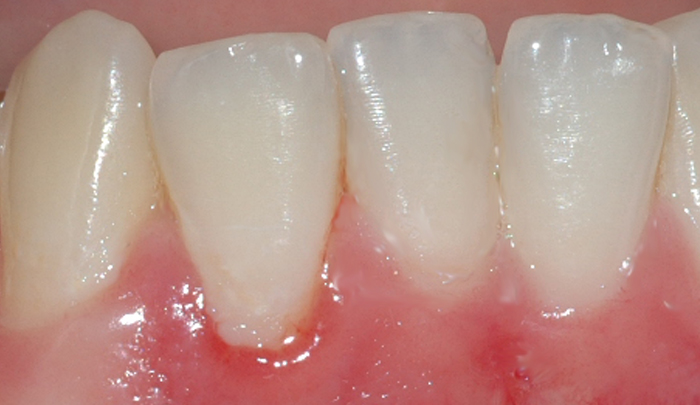

Et friskt tannkjøtt har lys rød farge og ligger stramt inntil tennene (fig. I). Et betent tannkjøtt får en mørkere rødfarge, det blir hovent og kan føles ømt ved berøring. Videre vil man kunne oppleve at tannkjøttet blør ved rengjøring og at det ligger mindre stramt inntil tennene.

Fig 1: Et friskt tannkjøtt har lys rød farge og ligger stramt inntil tennene Fig 2: Mangelfullt renhold kan over tid føre til utvikling av gingivitt

Mangelfullt renhold kan over tid føre til utvikling av gingivitt. Dette skyldes bakterier og mykt belegg (plakk) som blir liggende på tannen i kontakt med tannkjøttet (fig. II). Om man har mye tannstein, vil også dette kunne medvirke til utvikling av gingivitt. Gingivitt oppstår lettest mellom tennene og ellers der det er vanskelig å holde rent.